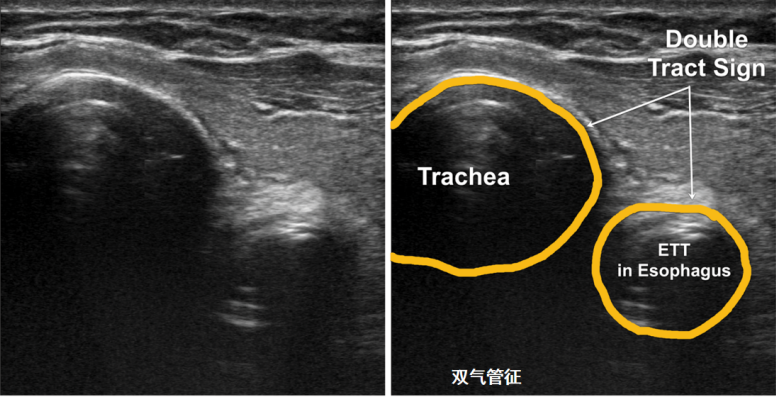

当气管插管进入气道后,在气道内壁可以看到一个典型的子弹头样的双轨征或子弹征,以此判断插管的位置。临床中在插管后扫查环状软骨切面,如果看到双轨征或子弹征(图17),即可确认气管插管在气道内。还可以将探头置于气道左侧, 食、颈动脉和气管围成的倒三角, 如果发现大的气道影和食影, 说明插管位置正确; 如果发现两个相同的气管影, 说明是双气管征(图18), 提示气管插管误入食

图18  双气管征

临床中我们可以通过一定的流程来判断插管的位置及深度,例如通过双气管征判断插管是否在气道内,通过肺滑动征是否对称来判断插管的深度。